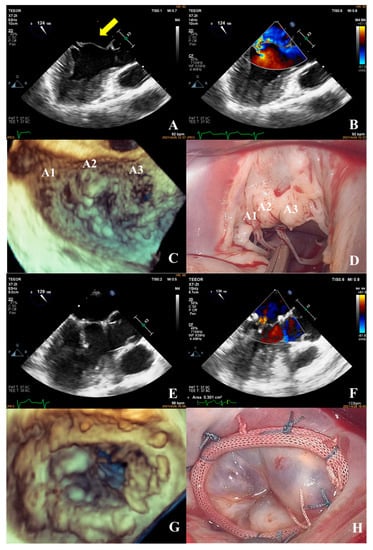

- Patients in the complex group had a variety of etiologies, including multiple segmental mitral valve prolapse (12.5%), Barlow’s syndrome (7.1%), infective endocarditis (12.5%), and rheumatic valvular heart disease (67.9%). The proportion of patients with each of the three less common etiologies was essentially the same. These diseases not only involve a wide range of lesions but are also accompanied by changes in valve morphology and structure, which increases the difficulty of surgery. Preoperative evaluation of the lesion is also a challenge for echocardiologists. A patient with preoperative suspicion of Barlow’s syndrome exhibited prolapse involving the A2 and A3 segments and posteromedial commissure, accompanied by redundant valve leaflets. The complexity score was 9 (2 × 2 + 2 + 3). Two artificial chordae tendineae were implanted in each of the A2 and A3 segments and a mitral annuloplasty ring was placed. The surgical technique score was 5 (4 × 1 + 1) and the surgical effect was good (Figure 9).